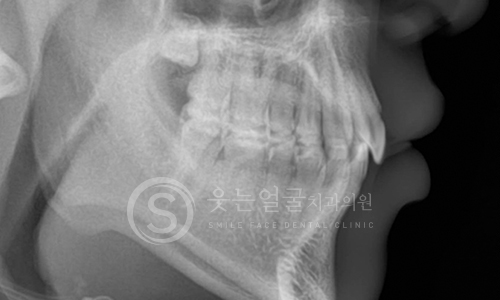

웃는얼굴치과의 12단계 교정진단시스템은 환자의 치아와 턱 구조,

얼굴 균형, 교합 상태 등을 체계적으로 분석하여

최적의 치료 계획을 수립하는 첨단 진단 프로세스입니다.

02 파노라마 촬영

03 세팔로 촬영

04 턱관절 검사

05 정면 X-ray 촬영